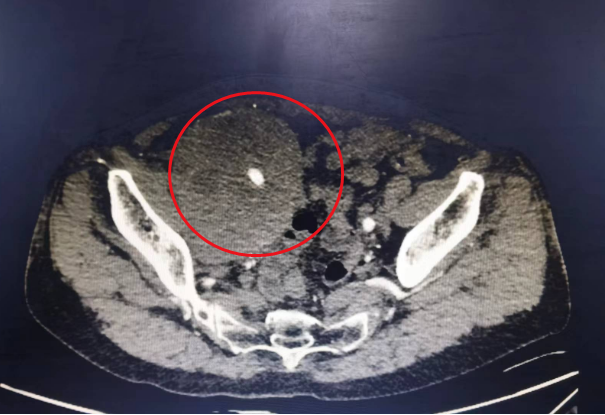

两年来,陈女士因为腹部胀痛曾在多家医院就诊,通过 CT 检查发现她的肚子里长了个香瓜般大小的肿块,且肿块包裹了腹腔血管、输尿管,彼此环绕互相渗透,这你中有我,我中有你的缠绵状态让手术难度增大、风险拔高。当地医院开腹探查后也无法切除肿块,束手无策之下只能终止手术,本以为一次手术就能解决问题的陈女士如坠深渊,在多方打听后到南溪山医院寻求帮助。

接诊的南溪山医院泌尿外科副主任医师尹三省介绍,治疗陈女士的难度主要有三点,首先是体内肿物巨大,血供丰富,同时包绕大血管,稍有不慎即可导致难以控制的大出血。再者,由于肿块长期压迫并包绕血管,不排除诱发血栓形成,手术操作时如果出现静脉血栓脱落,会导致致死性肺栓塞。最后就是陈女士已经做过一次开腹手术,腹腔粘连比较严重、组织分离困难。这些都直接让这个看似寻常的开腹手术难度瞬间升级。